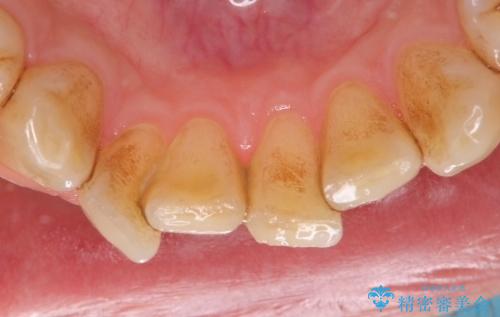

PMTCによる着色除去

- 着色が気になるとのことで来院された。

着色だけでなく、歯石やバイオフィルムの除去、ハイドロキシアパタイト配合のトリートメントで仕上げ磨きまで行います。